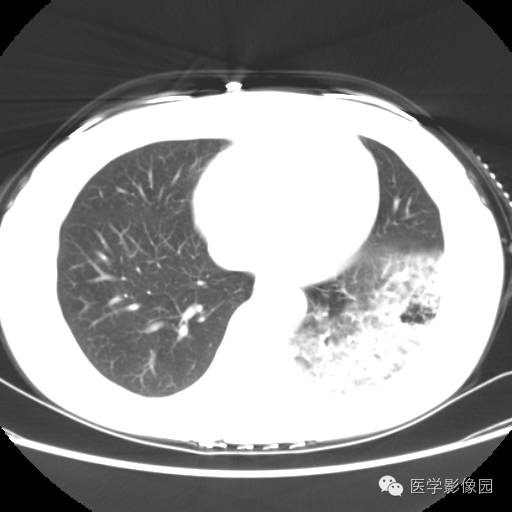

肺叶实变性支气管肺泡癌1例CT影像表现